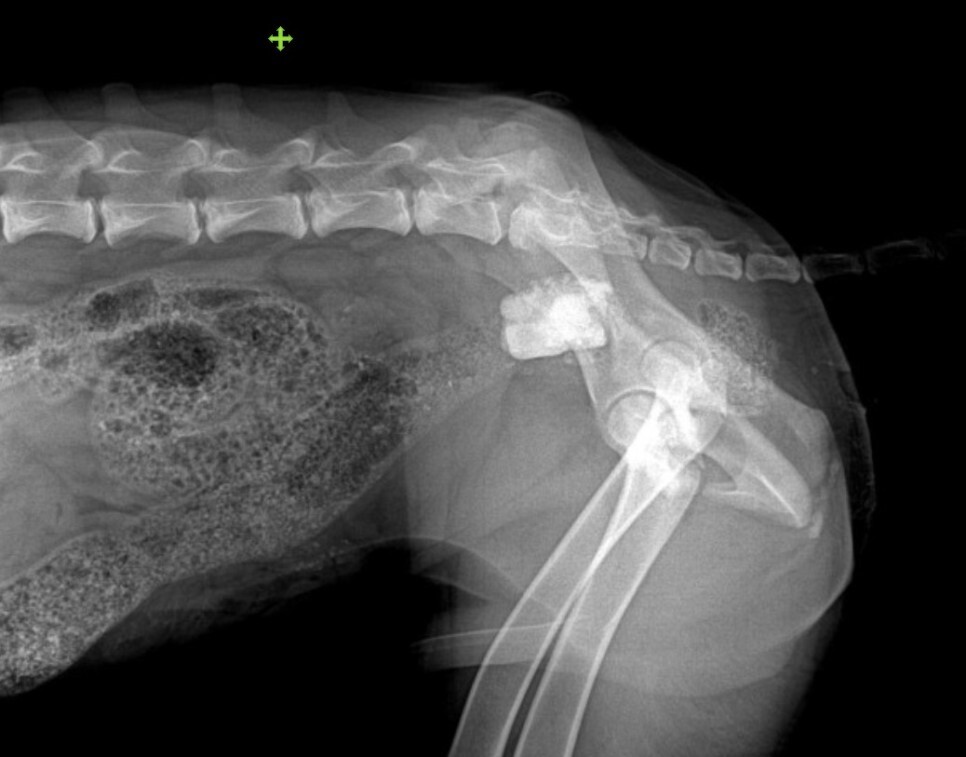

돌을 먹어서 장 부분 폐색으로 내원한 강아지입니다.

주 증상은 설사였습니다.

막혀 있던 돌을 제거하였고

분변 검사에서 과증식한 세균과 지알디아가 확인되어

항생제 치료를 진행하였습니다.

그러나 그 이후에도 설사가 멎지 않아

신선한 분변으로 검사를 다시 하였습니다.

검사 결과는 트리코모나스에 감염이 된 것으로

확인이 되었습니다.